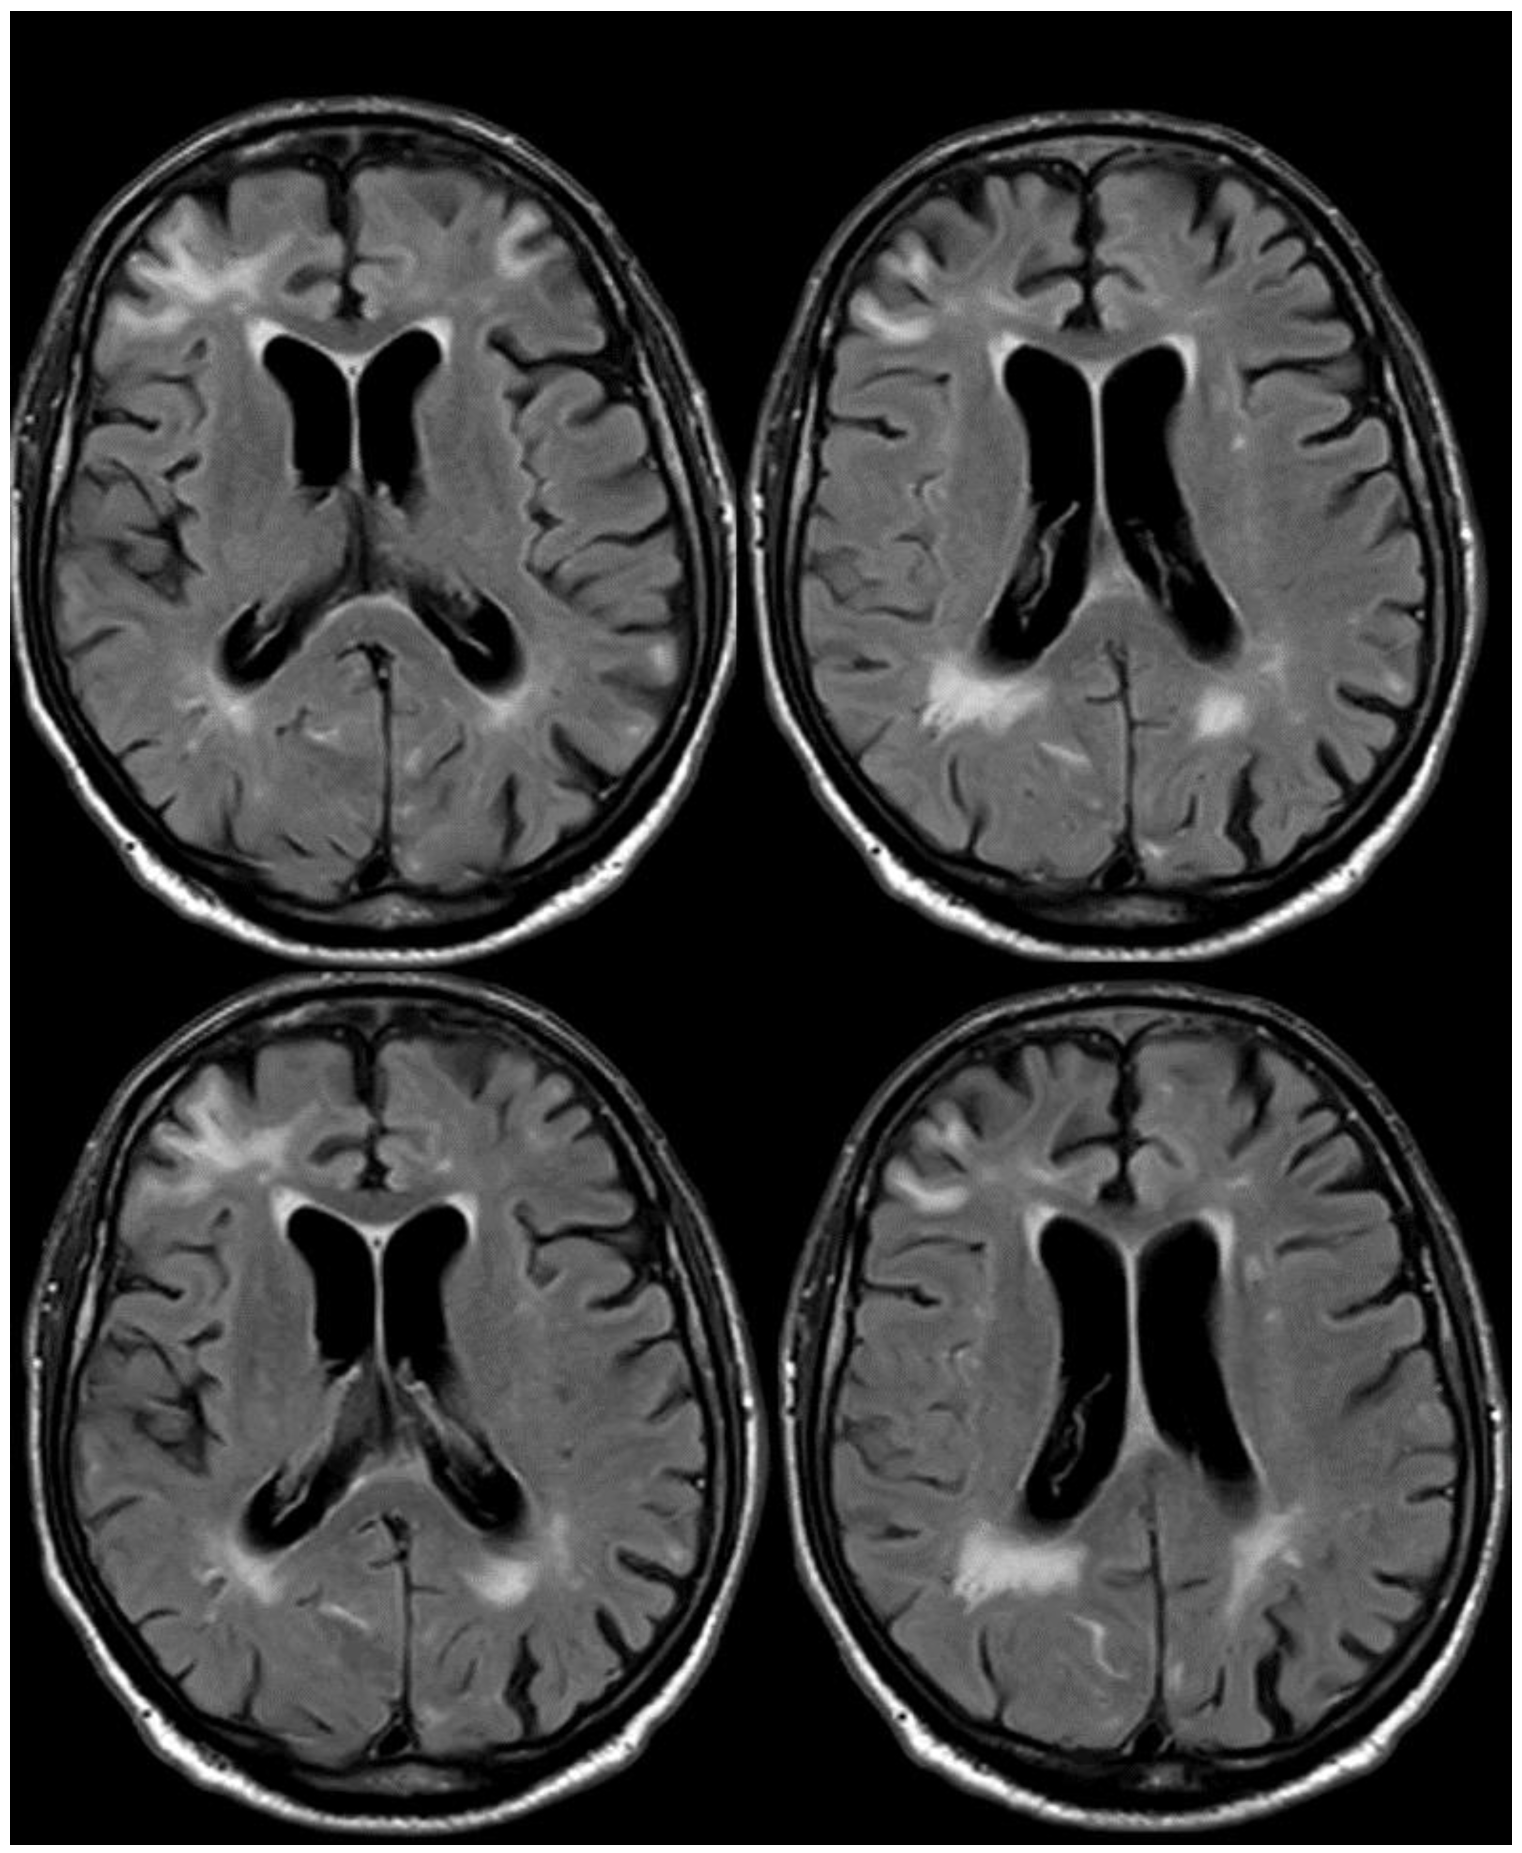

5. February 2017: First Recurrent CAA-Related Inflammation

6. December 2017: Recurrent SAH

7. April 2018: Second Recurrent CAA-Related Inflammation

8. April 2018: Third Recurrent CAA-Related Inflammation